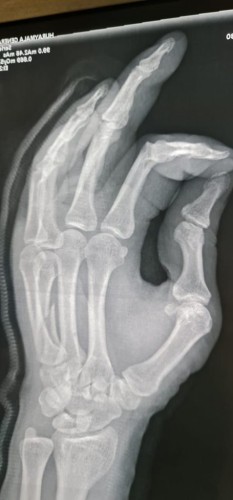

واستقبل قسم الطوارئ بالمستشفى المصاب حيث تم على الفور تشكيل فريق طبي مكون من أخصائيين قسم جراحة العظام والكسور بالمستشفى ، وقام الأطباء على الفور بعمل الإسعافات الأولية وإعطائه المحاليل والمسكنات والمضادات الحيوية، وتم عمل الأشعات العادية والمقطعية، التي أظهرت أن المريض يعاني من كسر متزحزح بالمشطية الرابعة لليد اليمنى ويحتاج تصليح مفتوح للكسر وتثبيت بشريحة ومسامير ذات طابع خاص، فتم نقل المريض إلى غرفة العمليات وإجراء عملية تثبيت بشرائح ومسامير.